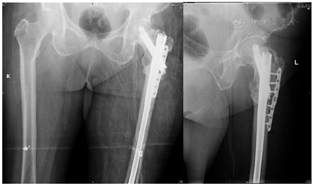

4.2016年3月双髋关节正侧位X线片 行左侧股骨粗隆下骨折闭合复位髓内针内固定术,骨折断端复位欠佳,骨折断端仍有间隙(图4)

5.2017年9月双髋关节正侧位片X线片 显示左侧股骨粗隆下骨折术后1年半,侧位片仍可见清晰骨折线,正位片提示内侧皮质鸟嘴样改变更为明显(图5)。